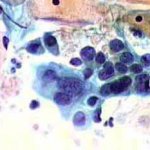

Δυσπλασίες τραχήλου μήτρας σοβαρού βαθμού (CIN III)

Ασυμπτωματική ασθενής 39 ετών. PH κόλπου 4,4. Κολποσκόπιση:

Στην δοκιμασία οξικού οξέως και στην δοκιμασία Lugol, αρνητική περιοχή, τόσο στο πρόσθιο, όσο και στο οπίσθιο χείλος του τραχήλου, σε ακτίνα 3-4 χιλ. και πλάτος περίπου 5 χιλ., με εικόνα διακριτικού επίπεδου μωσαϊκού.